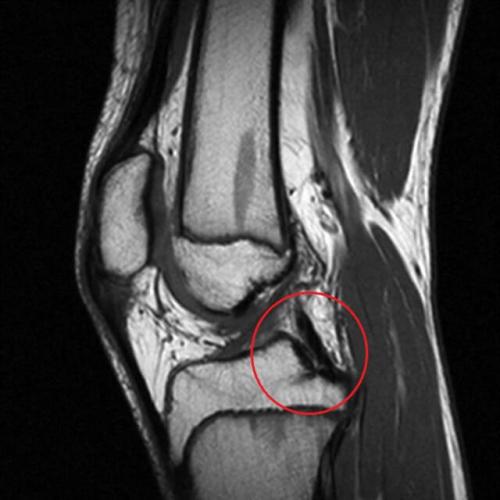

Рассекающий остеохондрит

Асептический некроз мыщелка бедренной кости из-за разрыва хряща и тонкого костного слоя под ним. Причиной является повышенная физическая активность, потому — боль в коленях у подростка или детей на фоне остеохондрита наблюдается при высокой спортивной активности.

Зачастую болезнь не дифференцируется с растяжением связок, что позже способно вызывать блокады колена и дальнейшие разрушения суставной поверхности.